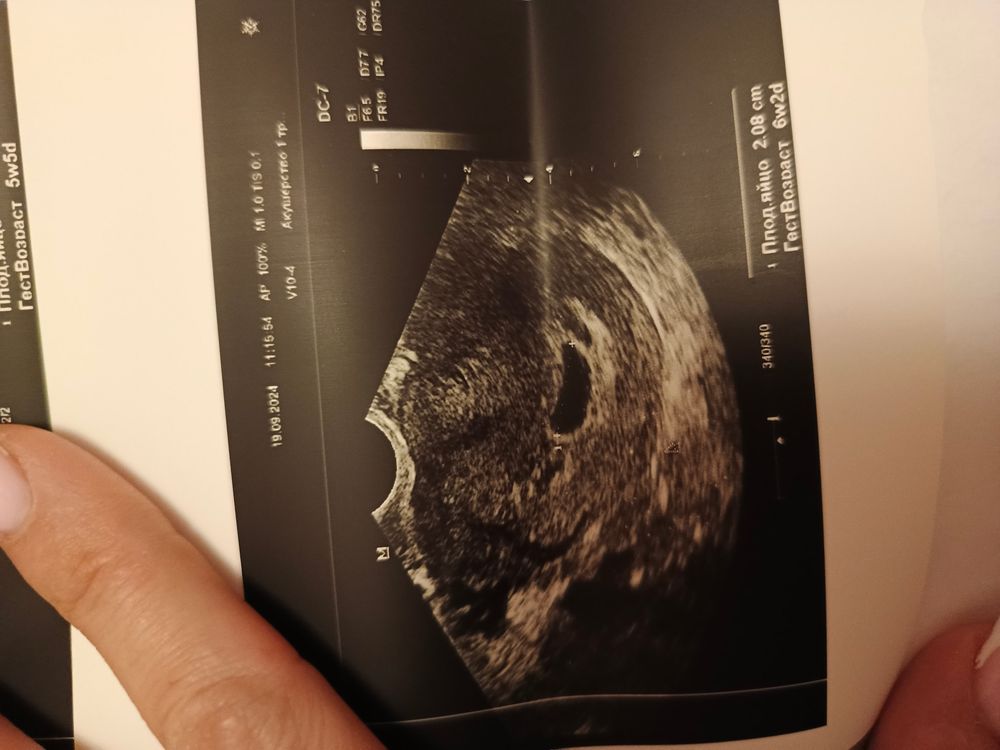

Ничего не пойму, на одном снимке плодное яйцо 1,75 на другом 2,08 и сроки разные,как такое может быть?

Замеряли разный диаметр. Срок высчитывает программа. Яйцо же плодное не прямо ровной круглой формы. Обычно пишут средний внутренний диаметр. То есть высчитывают по среднему и ставят срок

Потому что все замеры это примерно, есть погрешность. А на срок влияет каждый мм, 17 мм это один срок, 20 мм это уже другой срок. Тут другое странно, что на снимке такое большое ПЯ и как будто оно пустое, или может не видно просто